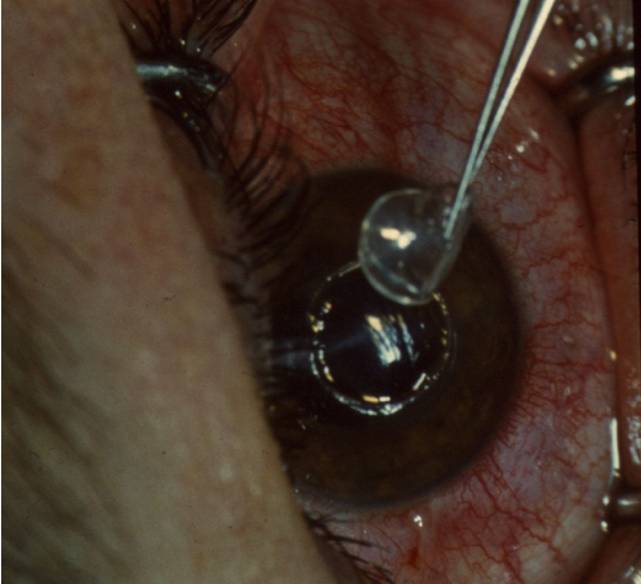

рис. 9.2.8), отмечая инъекционной иглой, смоченной 1% спиртовым раствором бриллиантовой зелени (см. рис. 9.2.9). Специальным отметчиком отмечают оптическую зону диаметром 6,0 мм (см. рис. 9.2.10). Сильный и слабый меридианы рефракции роговицы отмечают в области лимба перед подачей больного в операционную 1% спиртовым раствором бриллиантовой зелени по системе «Табо».С помощью отметчика роговицы (рис. 11.2.1) отмечают главные меридианы роговицы, затем определяют сектор сильного меридиана при простом миопическом астигматизме и по линии отметки оптической зоны производят насечку длиной до 1,0 мм на глубину 0,2 мм алмазным ножом с дозированной подачей лезвия, такую же насечку делают и в противоположном секторе (рис. 11.2.2) На глубине насечки специальным роговичным шпателем (рис. 11.2.3) делают расслаивание роговицы по линии отметки центральной зоны на % ее окружности. Точно такое же расслаивание проводят и в противоположном секторе. В сформированные тоннели микропинцетом вводят приготовленные заранее лентовидные трансплантаты с несколько заостренными краями и расправляют микрошпателем (рис. 11.2.4). Подсушенные трансплантаты имеют упругую консистенцию и легко вводятся в тоннели (рис. 11.2.5).

Рис. 11.2.4. Введение трансплантатов в секторальные тоннели

Рис. 11.2.5. Трансплантаты расположены в двух противоположных секторах